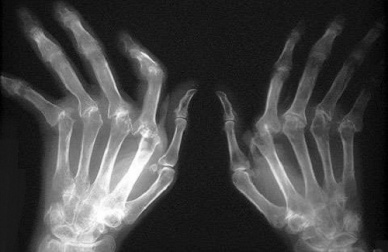

Le symptôme principal, et le plus visible, de l’arthrite rhumatoïde est l’inflammation des articulations, ce qui est généralement très douloureux pour la personne qui en est atteinte.

Il est d’ailleurs fréquent que les personnes souffrant d’arthrite rhumatoïde aient des sensations de raideur dans les articulations, surtout le matin.

Les zones les plus touchées par l’arthrite rhumatoïde sont :

- les poignets

- les coudes

- les épaules

- les doigts

- les orteils

- les hanches

- les chevilles

- les genoux

L’arthrite rhumatoïde peut aussi se compliquer et laisser apparaître des nodules rhumatoïdes, le plus souvent sur les mains et les pieds.

Il s’agit de petites bosses dures non douloureuses, issues d’une déformation des articulations et apparaissant au cours de l’évolution de l’arthrite rhumatoïde.